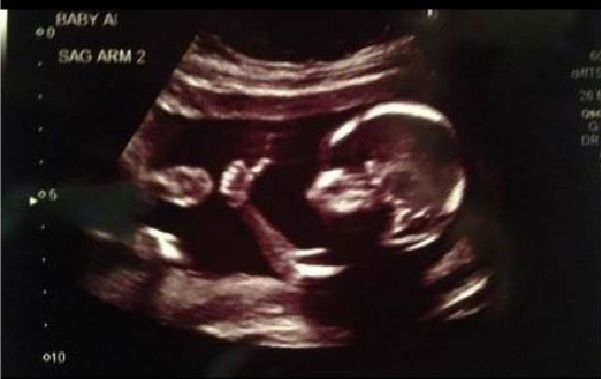

El curioso gesto de un feto de 18 semanas que aparece en su propia ecografía levantando el pulgar, en señal de que todo va bien, ha causado revuelo en el Reino Unido.

Esto, luego de que el padre del menor decidiera publicar la fotografía en la red social Reddit, donde alcanzó más de tres millones de visualizaciones en tan sólo 36 horas.

Sin embargo, esa no fue la única sorpresa, pues tras realizarse los estudios, los progenitores descubrieron que traerían al mundo a unos gemelos, y no a un solo bebé, como habían pensado hasta el momento.